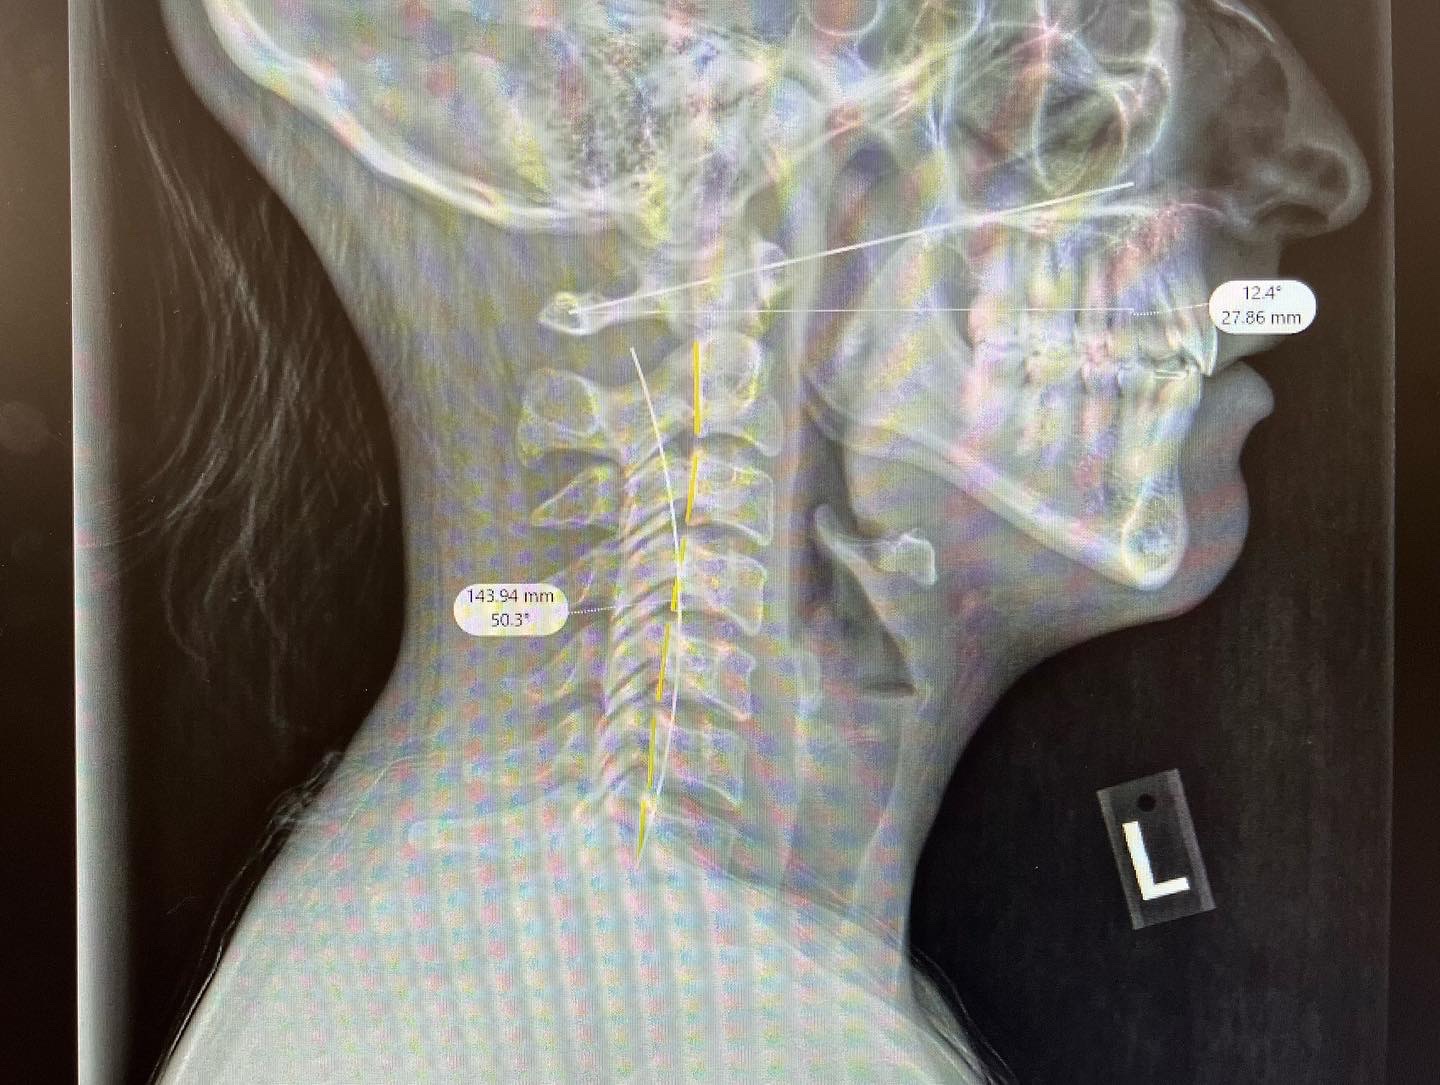

My name is Kate and I’m asking for help in raising money for a breast reduction. I’ve been large breasted most of my life (runs in the family) and I’ve reached a point where I’m experiencing more regular migraines that cause nausea, light and sound sensitivity . I’ve all but lost the curvature in my neck as shown in my Xray below. I need weekly appointments with my chiropractor to put my neck back into place. I’ve had two different consults with plastic surgeons here in the US and both times my insurance denied me. Out of pocket in the US is $18k-$20k for the reduction and lift. I did research and discovered that Turkey is one of the highest rated countries in the world for plastic surgery, specifically Istanbul. I’ve had a full consultation with the MayClinic and I’m trying to raise the cost to have the procedure in their clinic. This amount covers the entire procedure plus accommodation for 8 days, all transportation to/from airport/hospital/hotel, a nurse, checkups, pain medicine, surgical bra, a companion to come with me and breakfast each day. I currently wear a 36G and with this weight on my chest I’m worried what my neck health will be in 1 year let alone 10. Once I reach $1,000 I can set my appointment (this is the deposit price). My goal is to go in June or July 2026. Thank you for taking the time to read this.